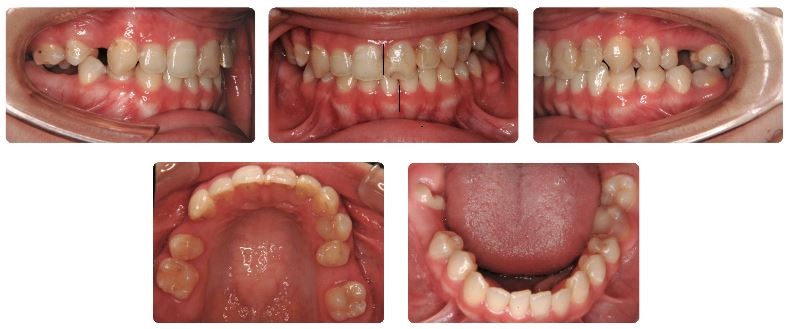

治療期間は3年2か月でした。

この症例は若年ということもあり矯正用アンカースクリュー(矯正用インプラント)の使用はしておりません。

治療過程の途中で幾度も来院間隔がかなり開いてしまいましたが、臼歯の移動と上下顎前歯の正中(真ん中)合わせを慎重に行いました。

上あご左側では6歳臼歯がすでに喪失していましたので親不知を生かすことで下あごの臼歯と咬合させました。